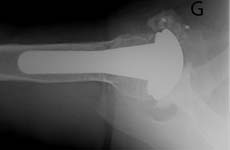

Radiographs include an anteroposterior view in the plane of the scapula an axillary view and a full humeral view all of high quality. Here is an AP view and an axillary view showing a glenoid component that has completely loosened from the bone and is floating free within the joint (two white dots near the letter "G"). [See Figures 19 20]

In cases of instability, examination under fluoroscopy may be useful. The radiographic evaluation must confirm the type and size of components, their position, and the nature of their fixation to bone. The preoperative plan must include a definitive plan for removal of the glenoid and humeral components, should this prove necessary, as well as a plan for reconstruction of the humerus and the glenoid after prosthesis removal. If removal of a cemented humeral component may be necessary, it is essential to have a full set of cement removal tools, a high speed saw capable of cutting a prosthetic stem fluoroscopy, and long stem prostheses of all possible sizes. The possible need for bone and tendon graft is also anticipated.